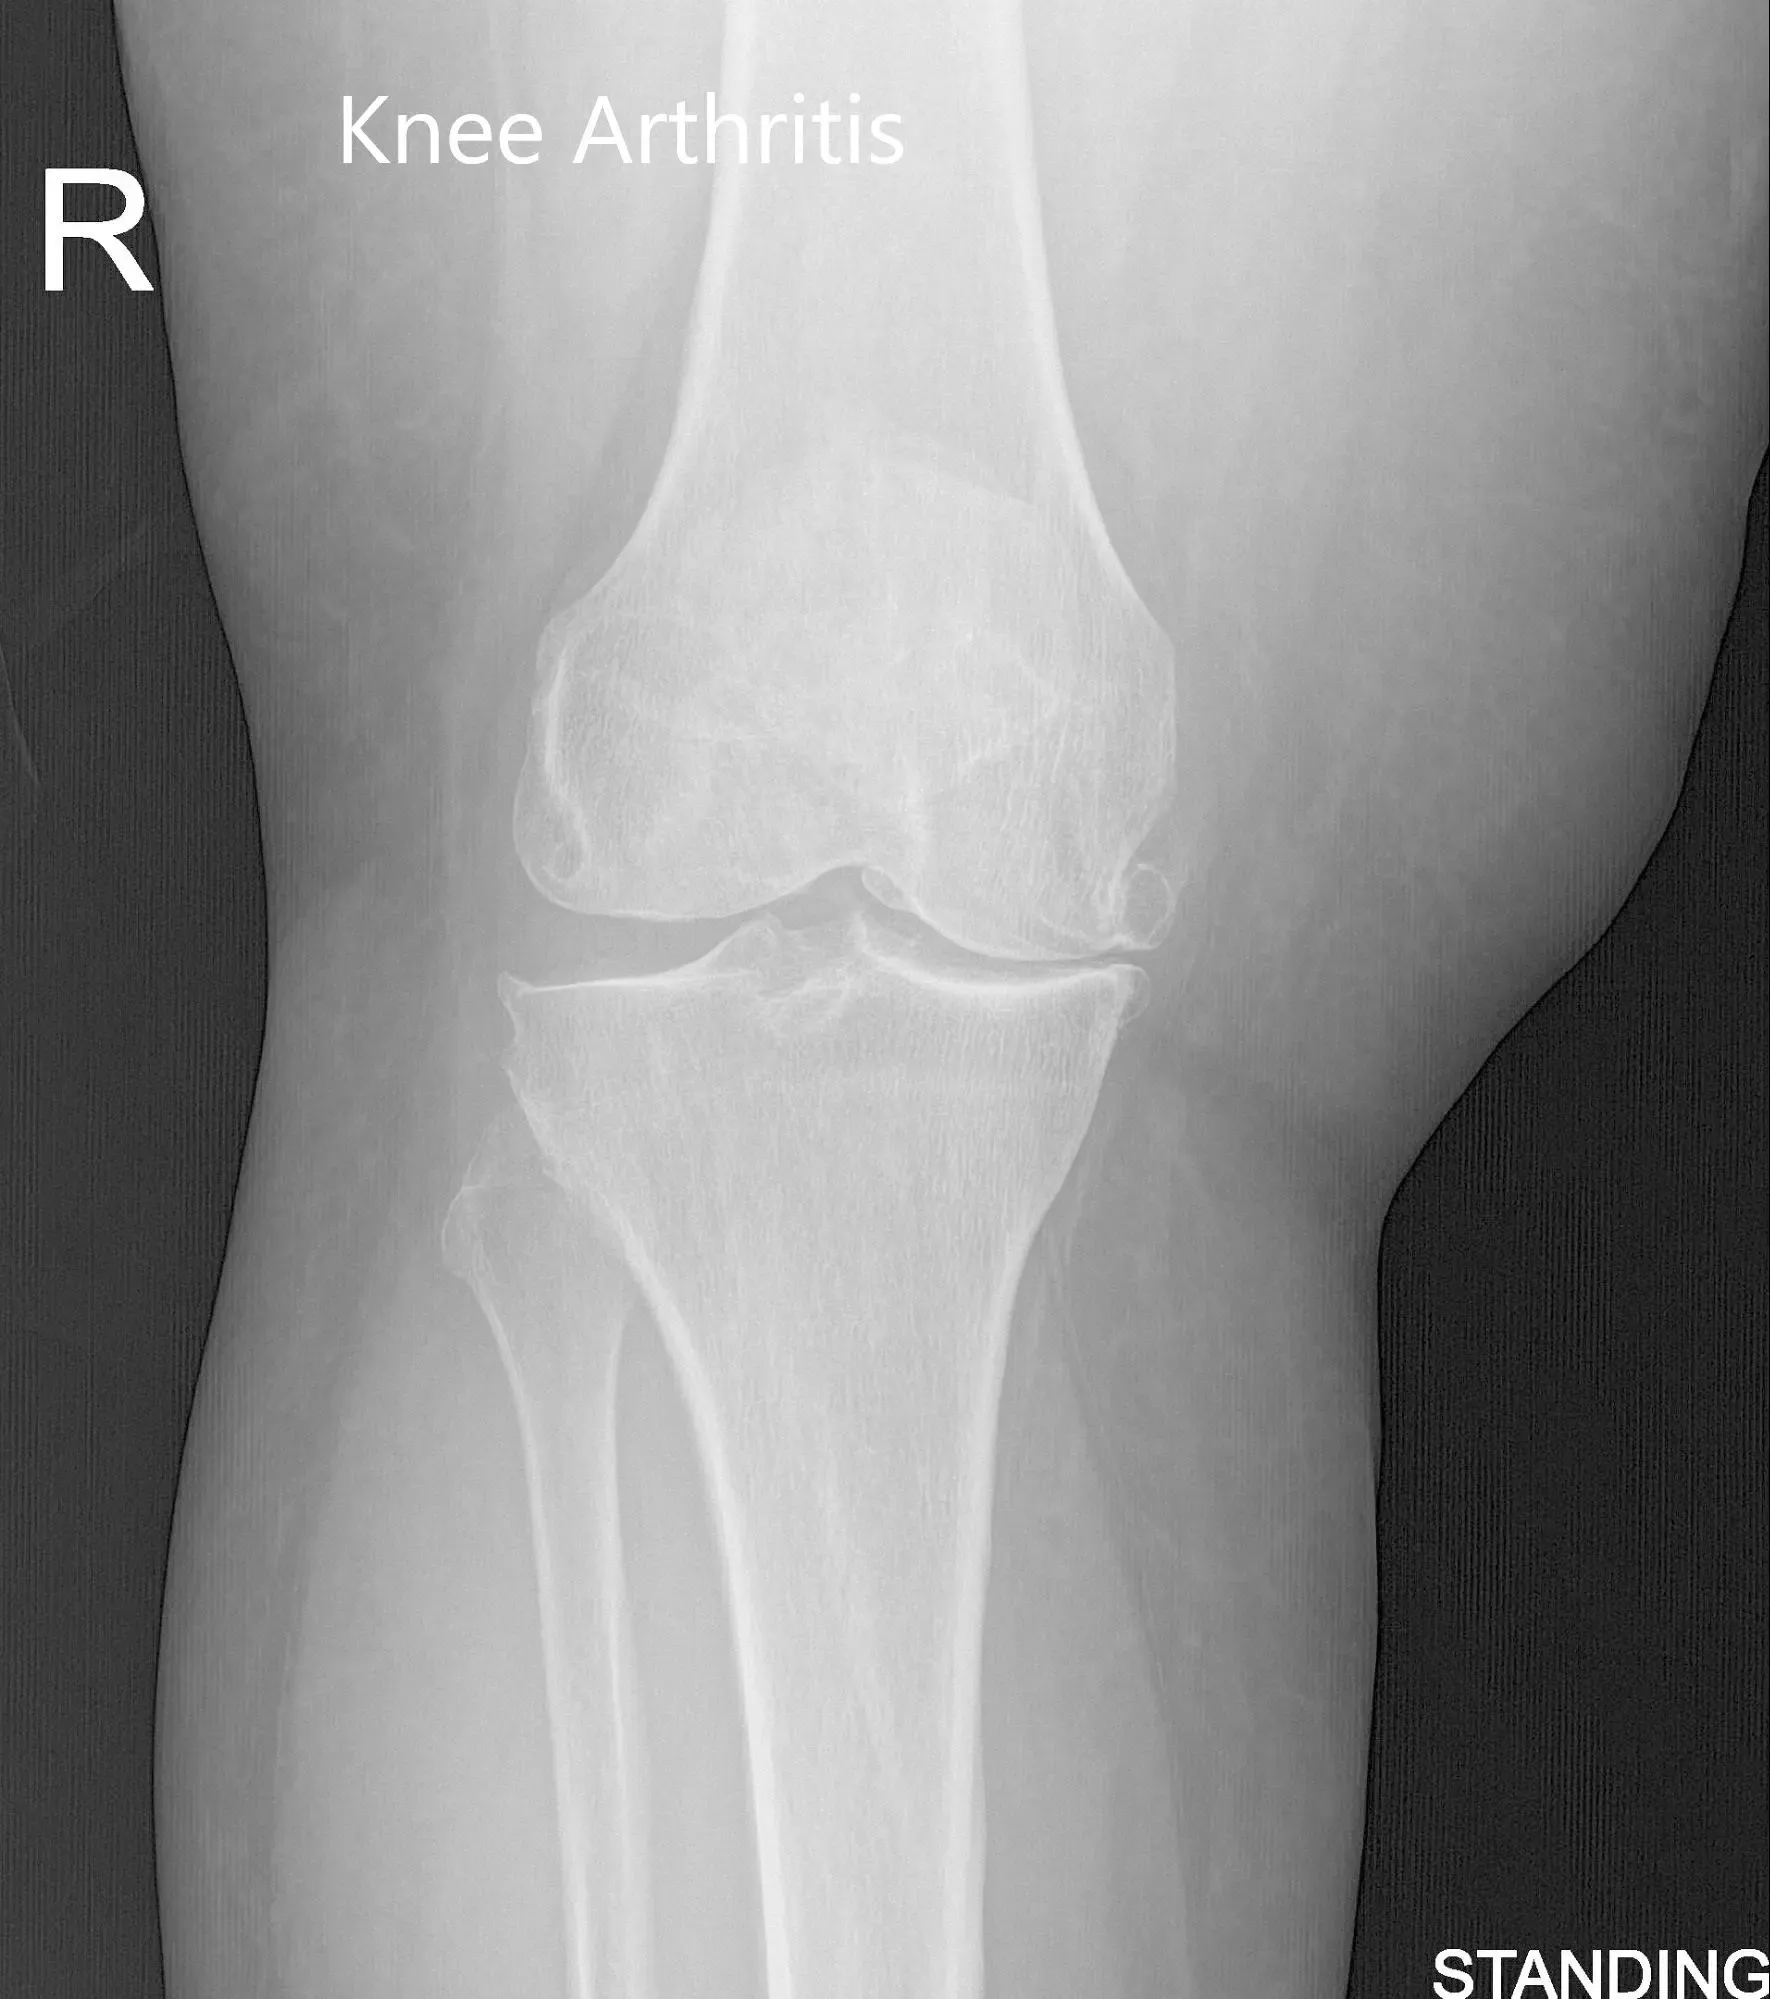

Pre-Operative AP and Lateral X-Ray views of the Right Knee

A 71-year-old female presented to our office with complaints of bilateral knee pain (right greater than left) for the past four years. The patient stated that the pain was getting worse over time despite conservative management in forms of physical therapy, knee injections, and pain medications. The pain severely affected his daily activities such as walking and climbing stairs.

The patient was assessed at the office for surgical management of knee arthritis and was found a suitable candidate for total knee arthroplasty of the right knee. The patient was offered a custom knee replacement system. Risks, benefits, and alternatives were discussed thoroughly, and the patient went ahead for the procedure. The custom knee replacement system includes custom patient-specific implants with custom instrumentation.